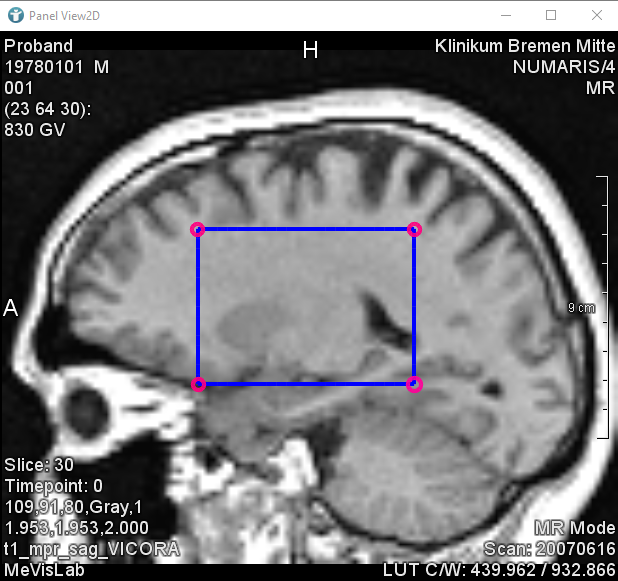

In the next image, you can see a rectangular shaped CSO. The pink circles you can see are called Seed Points.

Seed Points define the shape of the CSO. In the case of a rectangle, you need four Seed Points forming the corners to define the whole rectangle.

The points forming the blue lines are called Path Points.

The Path Points form the connection between the Seed Points whereby contour objects (CSOs) are generated. CSOs are often closed, but do not need to be.

In general, the Seed Points are created interactively using an editor module and the Path Points are generated automatically by interpolation or other algorithms.